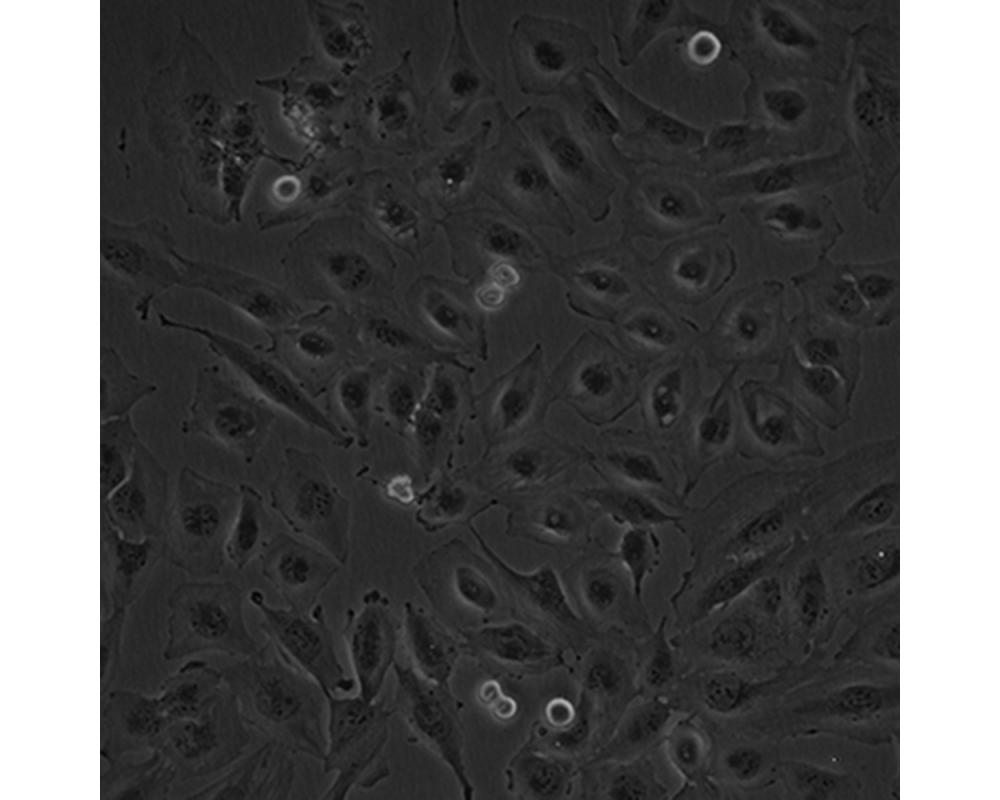

中文名稱 人腦髓母細(xì)胞瘤細(xì)胞

組織來(lái)源 成神經(jīng)管細(xì)胞瘤;男性

形態(tài)特征 多邊形

生長(zhǎng)特性 貼壁生長(zhǎng)

特征特性 該細(xì)胞是1985年由Jacobsen PF建立的,源自一名4歲大的兒童的后顱窩腫瘤的活檢組織,未檢出神經(jīng)元和膠質(zhì)分化的特征;可用作轉(zhuǎn)染宿主。